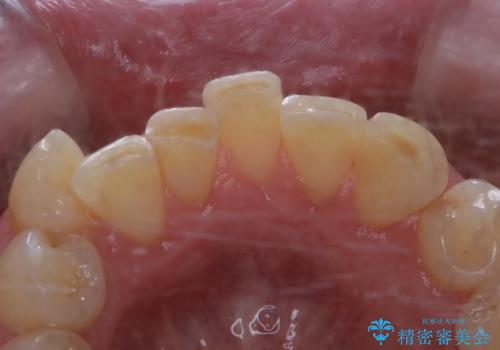

被せ物治療が終了したため全体的にクリーニングを

- 被せ物の治療が終了したためメンテナンスに入る前に全体的なチェック・クリーニングを行いました。

歯科衛生士による専門的なクリーニングPMTC(保険外治療)60分コースを行いました。

専門的な機械・材料を使用して徹底的に汚れを取り除きました。

染め出しをして、磨き残しの確認・ブラッシング指導も行いました。